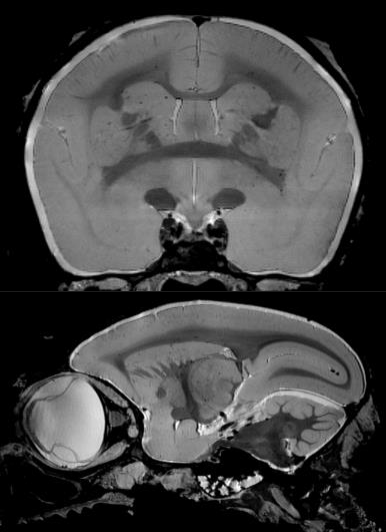

1、高分辨率神經(jīng)解剖結(jié)構(gòu)

布魯克結(jié)合超高磁場(chǎng),先進(jìn)的相陣控線圈和譜儀技術(shù)提供完美品質(zhì)的結(jié)構(gòu)形態(tài)成像。超高空間分辨率可以顯示精細(xì)的顯微組織結(jié)構(gòu)。領(lǐng)先的磁共振成像技術(shù)在超高磁場(chǎng)下提供完美的對(duì)比度。

磁共振成像低溫探頭增加150%的靈敏度,清晰顯示小鼠腦部細(xì)胞層狀結(jié)構(gòu)(小腦的顆粒層和浦肯雅細(xì)胞層),空間分辨率達(dá)到 50μm: